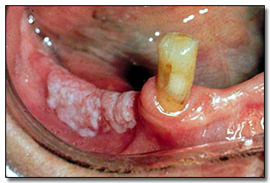

Kronik Hiperplastik Kandidiyazis

Mukozadaki beyaz plaklar kalın ve yapışıktır. Pamukçukta olduğu gibi kaldırılamazlar.